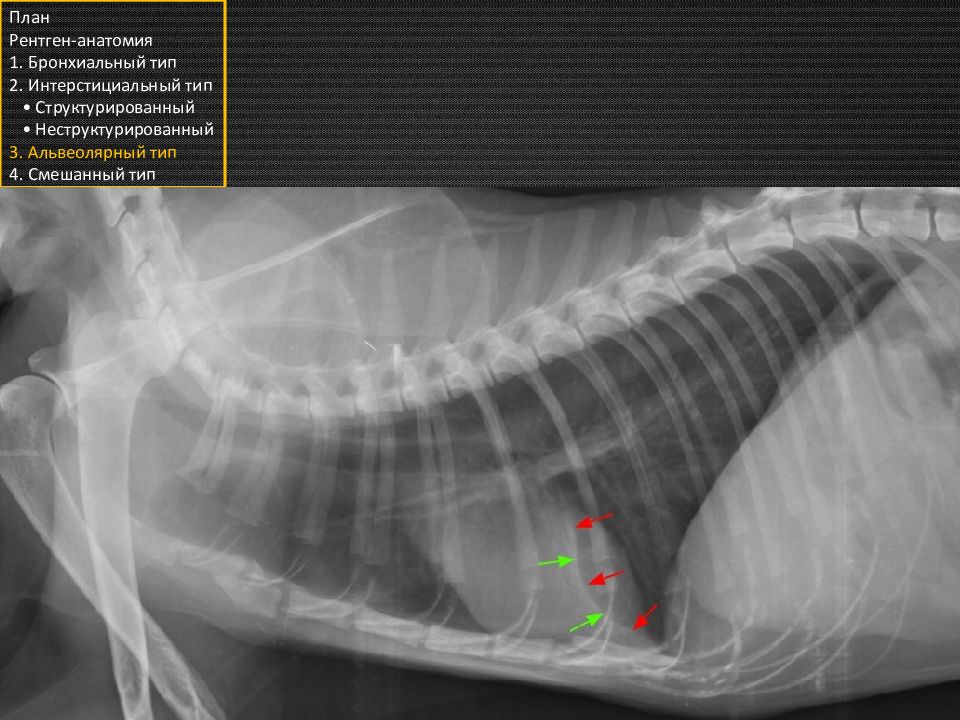

При значительном заполнении альвеол, возникает признак воздушной бронхограммы: газ в долевом бронхе чётко визуализируется на фоне безвоздушного лёгкого (отмечено стрелками). План Рентген-анатомия 1. Бронхиальный тип 2. Интерстициальный тип • Структурированный • Неструктурированный 3. Альвеолярный тип 4. Смешанный тип